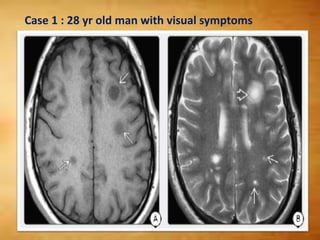

Case 1 : 28 yr old man with visual symptoms

Case 1 :28 yr old man with visual symptoms